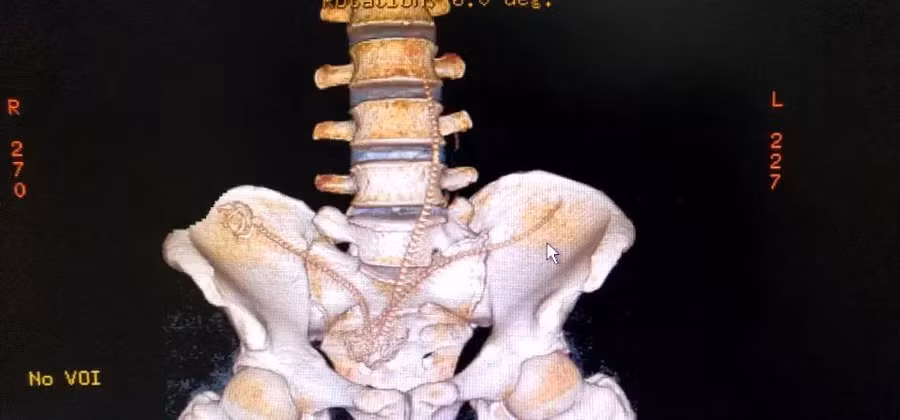

Kết quả tái tạo của chụp CT 3 chiều chỉ rõ vị trí 3 con cá.